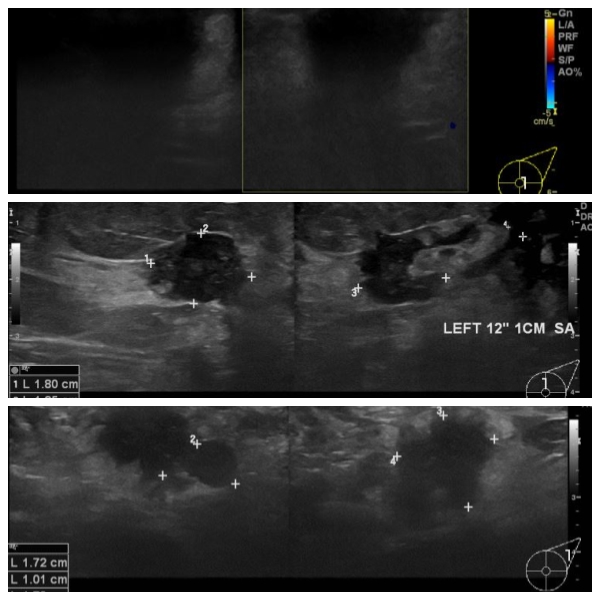

좌측 유방에 만져지는 멍우리로 내원하신 70대 여성분으로 본원 초음파 시행 후

좌측 3시 방향 유두 밑과 12시 방향 1cm 떨어진 거리의 혹 중앙핵생검 시행하여 좌측

침윤성 유관암 진단 되었으며, 좌측 겨드랑이 림프절비대 세침검사 시행하여 전이암

진단 되었습니다.